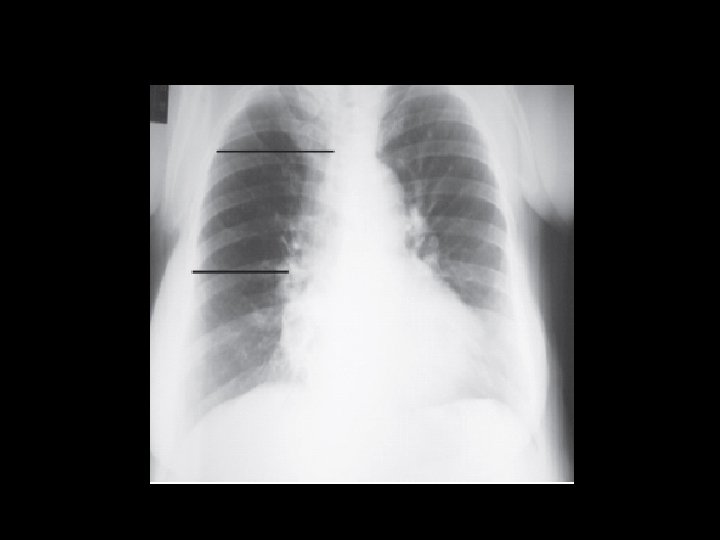

CASO CLÍNICO – PARTE III “O exame solicitado é realizado e está mostrado na imagem abaixo: ” QUAL O DIAGNÓSTICO PROVÁVEL?

DIAGNÓSTICO DISSECÇÃO AÓRTICA AGUDA